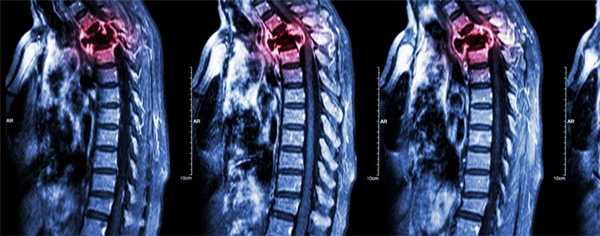

- нарушение двигательной активности вплоть до паралича возможно при сдавлении спинного мозга в шейном отделе остеобластическим очагом или повреждении отломками при литическом разрушении.

Дополнение химиотерапии локальным облучением позволяет повысить общий результат терапии, снять боль и уменьшить вероятность перелома. Так при поражении шейных позвонков лучевая терапия обязательна уже на первом этапе.

Компрессия спинного мозга

Компрессия спинного мозга выявляется у 1-5% пациентов с метастатическими поражениями позвоночника. В 70% случаев причиной нарушений становятся метастазы в грудные позвонки, в 20% - в поясничные и крестцовые позвонки, в 10% случаев – в шейные позвонки. При метастазах в кости могут выявляться как острые (при сдавлении костным фрагментом), так и постепенно прогрессирующие (при сдавлении растущей опухолью) расстройства. При сдавлении растущим новообразованием пациентов с метастазами в кости беспокоят нарастающие боли. Развивается мышечная слабость, выявляются нарушения чувствительности. На заключительной стадии возникают парезы, параличи и нарушения функции тазовых органов.

При сдавлении фрагментом кости клиническая картина компрессии спинного мозга развивается внезапно. На начальных стадиях оба вида компрессии обратимы (полностью или частично). При отсутствии своевременной медицинской помощи в течение нескольких часов или дней паралич становится необратимым. Своевременное адекватное лечение позволяет уменьшить выраженность симптомов, однако восстановление способности к самостоятельному передвижению отмечается всего у 10% больных с уже развившимся параличом.